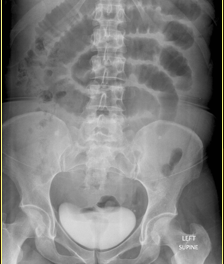

Which one is small v. latge bowel obstruction?

top: small bowel w/valvulae conniventes

bottom: large bowel w/haustrations